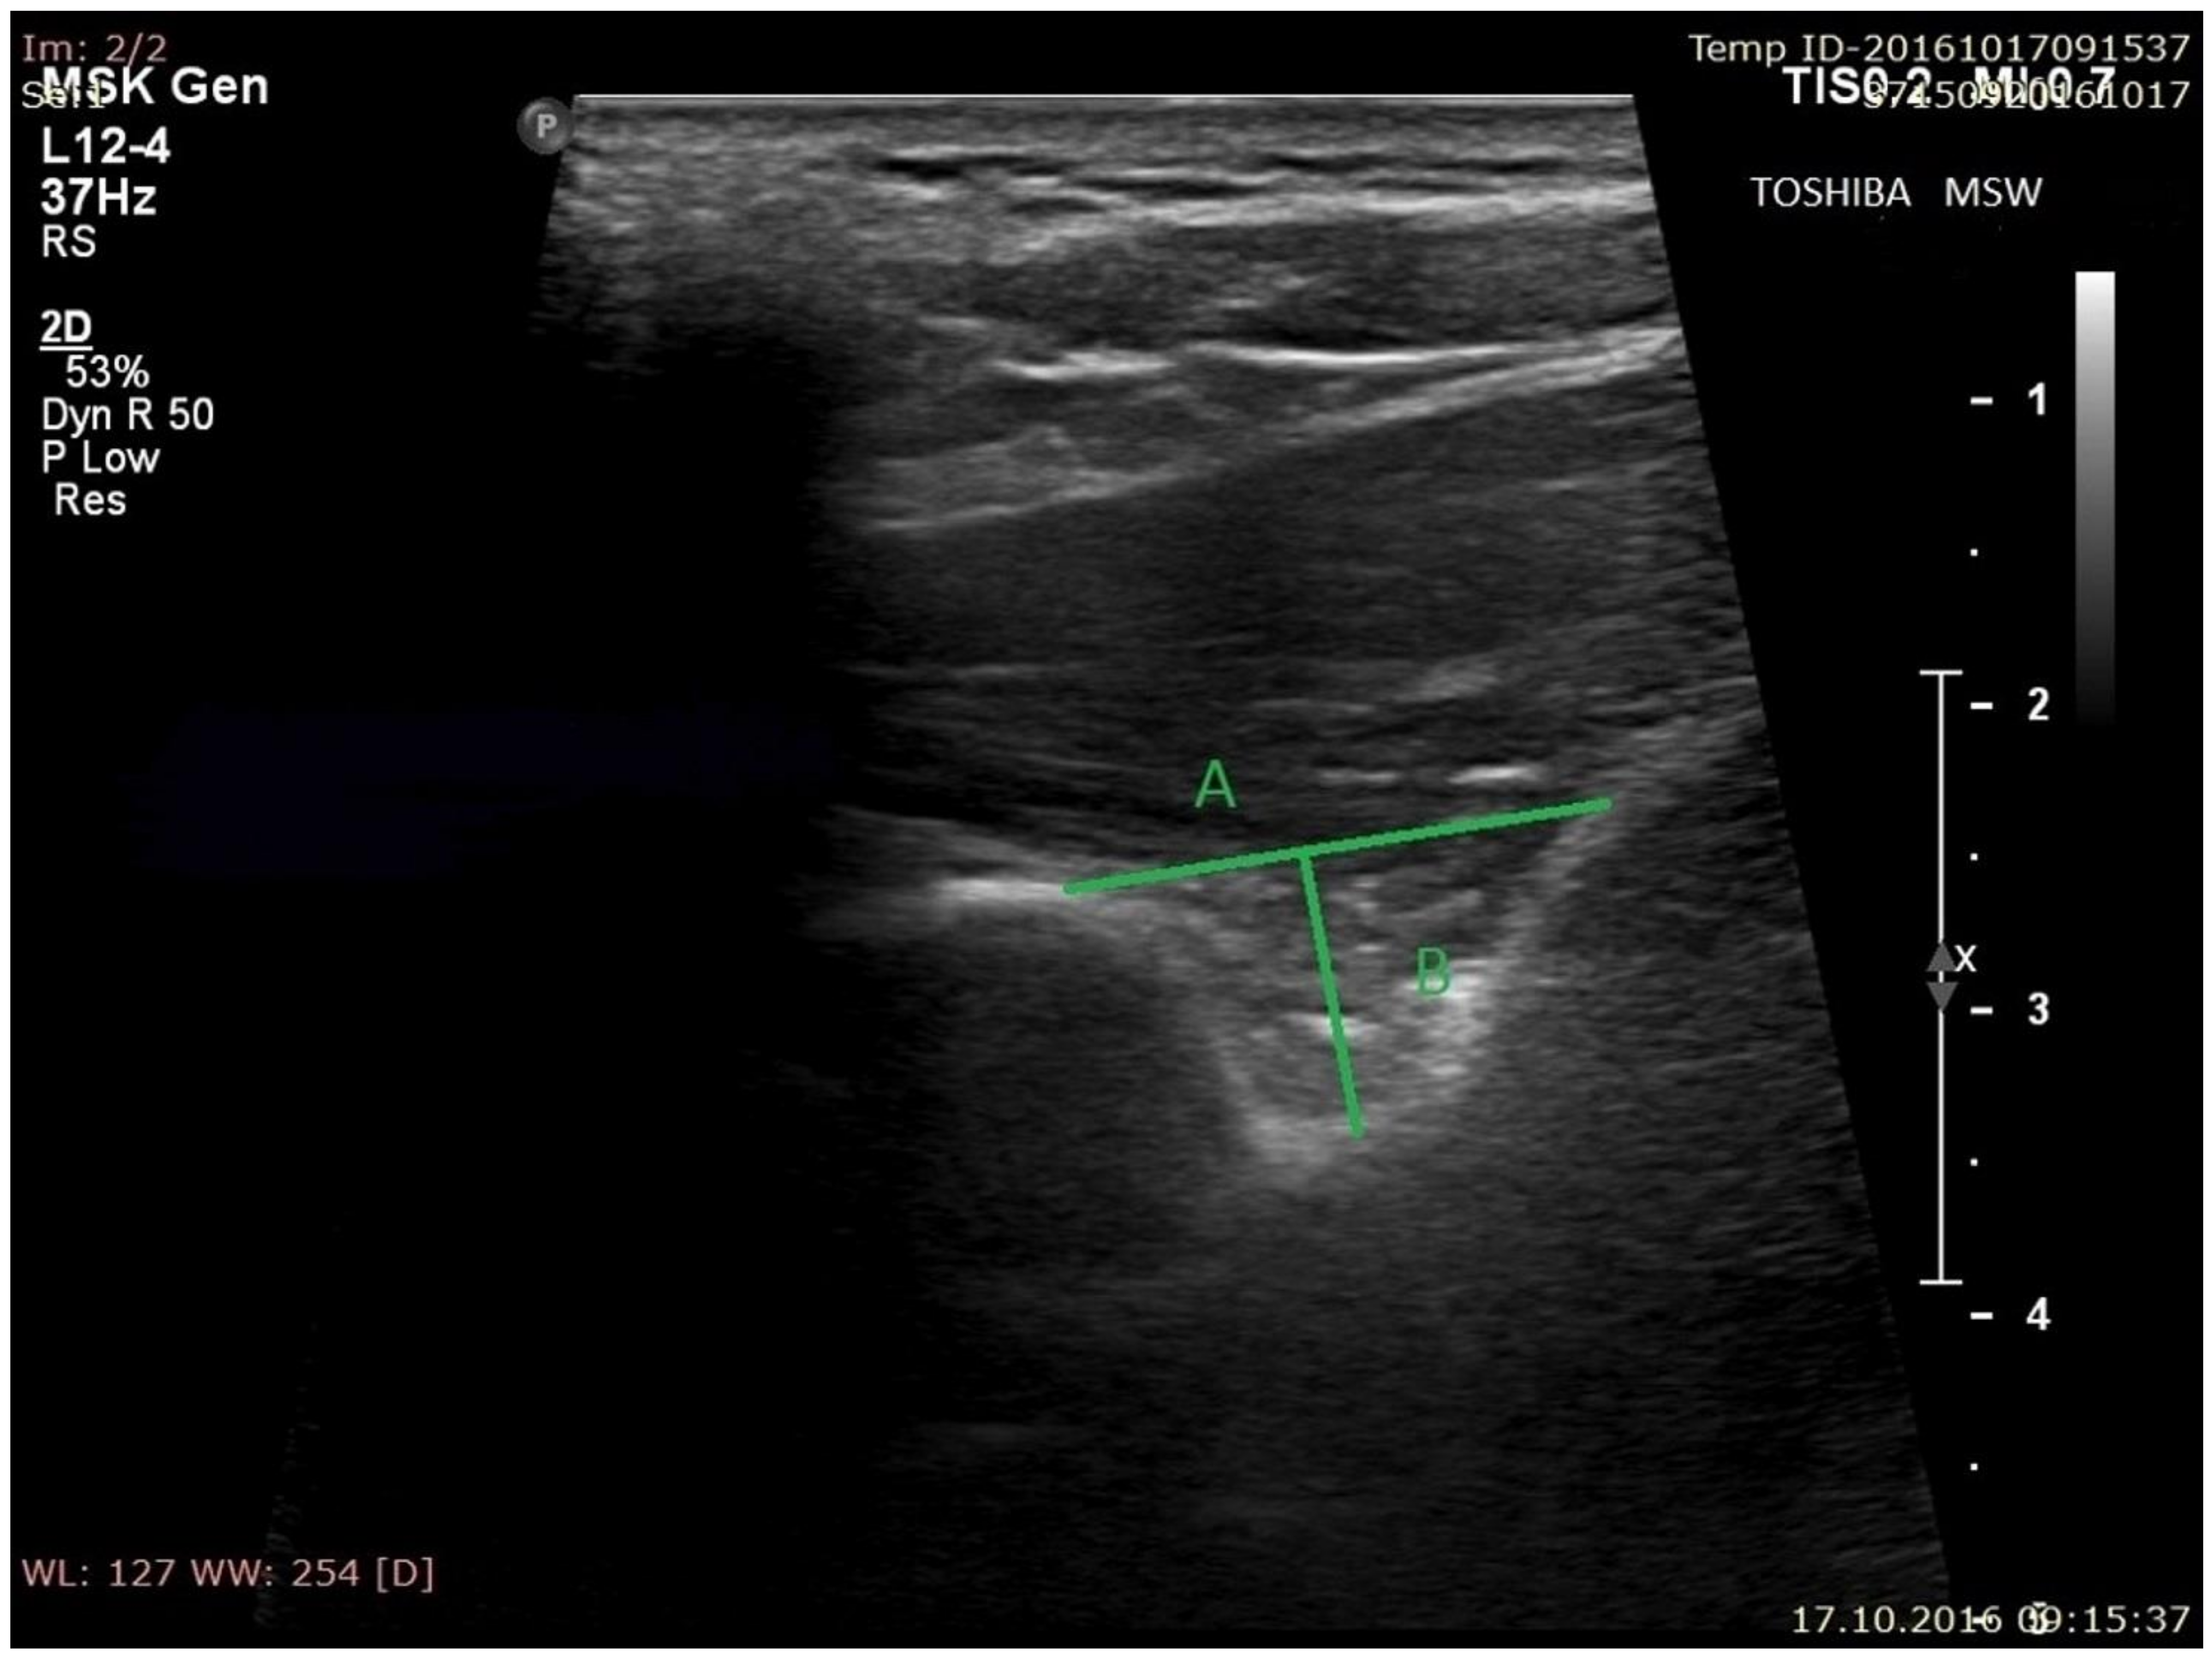

Figure 2. Measurements of suprascapular notch during ultrasonographic investigation. (A) the superior transverse diameter (STD); (B) the maximal depth (MD). - (b)

- the superior transverse diameter (STD) of the suprascapular notch: the maximal distance in the horizontal plane between the corners of the suprascapular notch (Figure 2).

- the maximal depth (MD) of the suprascapular notch: the distance between the STD and the deepest point of the suprascapular notch measured in a plane perpendicular to the STD (Figure 2).